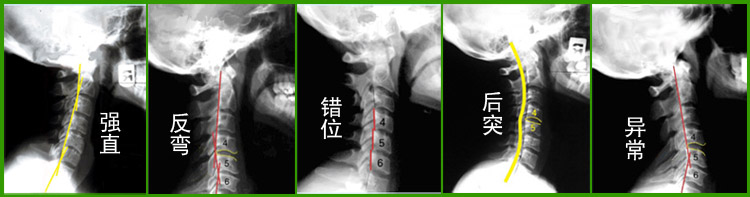

什么是颈椎曲度反弓

颈椎反弓案例.png

颈椎反弓

颈椎反弓图片